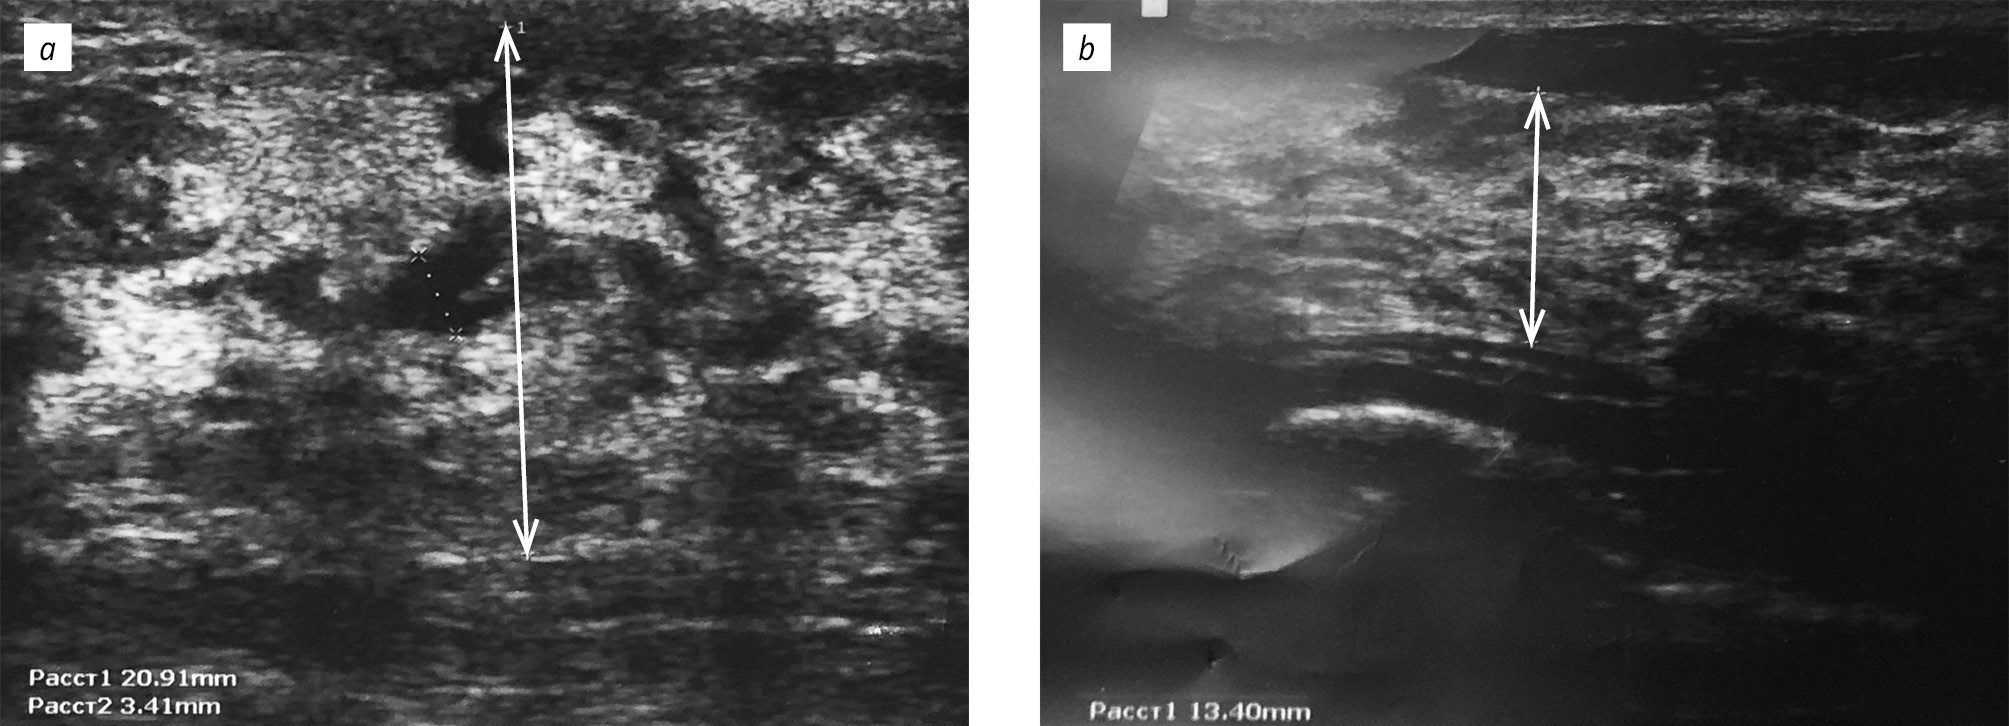

Через 6 мес. приема метформина эхогенность паренхимы молочных желез стала средней у 90,9 % пациенток первой группы и 88,9 % пациенток — второй, также произошло достоверное уменьшение толщины паренхимы молочных желез (рис. 3) и диаметра млечных протоков (см. табл. 1).

Рис. 3. Толщина железистого слоя: а — до начала терапии метформином; b — через 6 мес. терапии

Fig. 3. Thickness of the glandular layer: a — before metformin therapy; b — after 6 months of metformin therapy